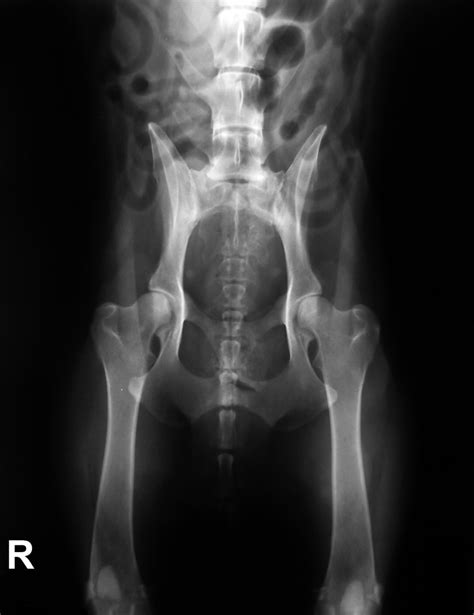

Ochorenie sa dá zdiagnostikovať a určiť stupeň dysplázie jedine RTG vyšetrením vykonanom v celkovej anestézii na oficiálne schválenom RTG pracovisku. Od 12 týždňov veku je možné vykonať tzv. rannú diagnostiku DBK. V prípade podozrenia na dyspláziu sa diagnostika vykonáva ihneď bez ohľadu na vek.

Pri vyšetrení sa sleduje laxicita kĺbov a následne pri rntgenologickom vyšetrení sa meria miera pohyblivosti kĺbovej hlavice ku kĺbovej jamke. Na Slovensku sú momentálne do chovu uznané len psy so stupňom 0 a 1, resp. A 0/0 - B 1/1. Pre účely chovnosti je jedinec vyšetrovaný po dosiahnutí určitého veku (v závislosti od plemena od 12,18, či 24 mesiacov). Po posúdení RTG snímku na chovné účely je vyhodnotený certifikát s výsledkom, ktorý je zároveň zapísaný aj do PP. Na hodnotenie sa u nás (podobne ako vo väčšine európskych krajín) používa 5-stupňový systém, škála hodnotenia je od A - E alebo 0 až 4. Dysplázia bedrového kĺbu sa medzinárodne označuje ako HD (hip dysplasia). Vyhodnocuje sa ľavý i pravý kĺb, zápisy HD 0/0 alebo HD A/A predstavujú zdravé kĺby bez nálezu. Čím vyššie číslo (resp. písmeno), tým vyšší stupeň dysplázie.

Na diagnostiku ochorenia sa používa röntgenové vyšetrenie za pomoci RTG prístroja. Pre komplexné posúdenie stavu bedier je potrebné vyšetrenie vykonať v úplnej anestézii. Anestézia je potrebná z dôvodu uvoľnenia svalov a dosiahnutia najlepšej polohy pre RTG vyšetrenie bedier. Diagnostiku je možné vykonať už od 12 týždňov veku šteniatka. V závislosti od predispozícii a konkrétneho plemena sa vyšetrenie môže opakovať po dosiahnutí 3, 12 alebo 24 mesiacov.

Chov ČsV a DBK: Podmienkou uchovnenia československého vlčiaka je aj vyšetrenie na toto ochorenie. Vyhodnotenie robí len jeden veterinár na Slovensku, aby zostalo objektívne. Vyšetrenie sa robí pomocou RTG, je bezbolestné. Snímky sa zhotovujú z oboch kĺbov, ako u DBK, tak u DLK, jednak pre porovnanie kĺbov a tiež, že je vysoko pravdepodobné, že poškodené sú oba kĺby.